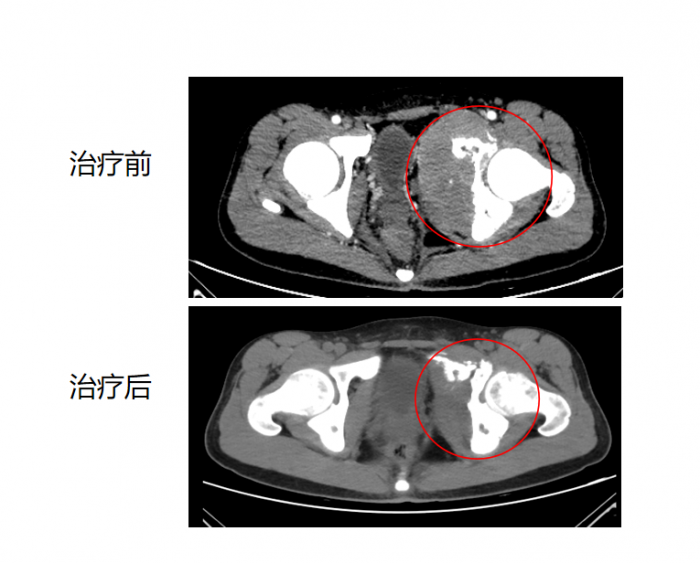

接诊后,肿瘤一科主任谢开红带领团队迅速完善相关检查,确诊肿瘤复发,盆腔巨大肿块并广泛侵犯骨骼。结合小远的病情和身体状况,决定采用国际先进的空间分割放疗技术联合药物系统治疗,为其量身定制个性化治疗方案。

治疗期间,主治医生朱欢密切监测小远的身体反应,及时调整治疗参数,确保方案精准适配个体需求。经过5次空间分割放疗及后期的药物治疗,小远的疼痛症状完全消失,复查显示肿块明显缩小,现在不仅能正常行走,还能进行适量运动,生活质量实现质的飞跃。